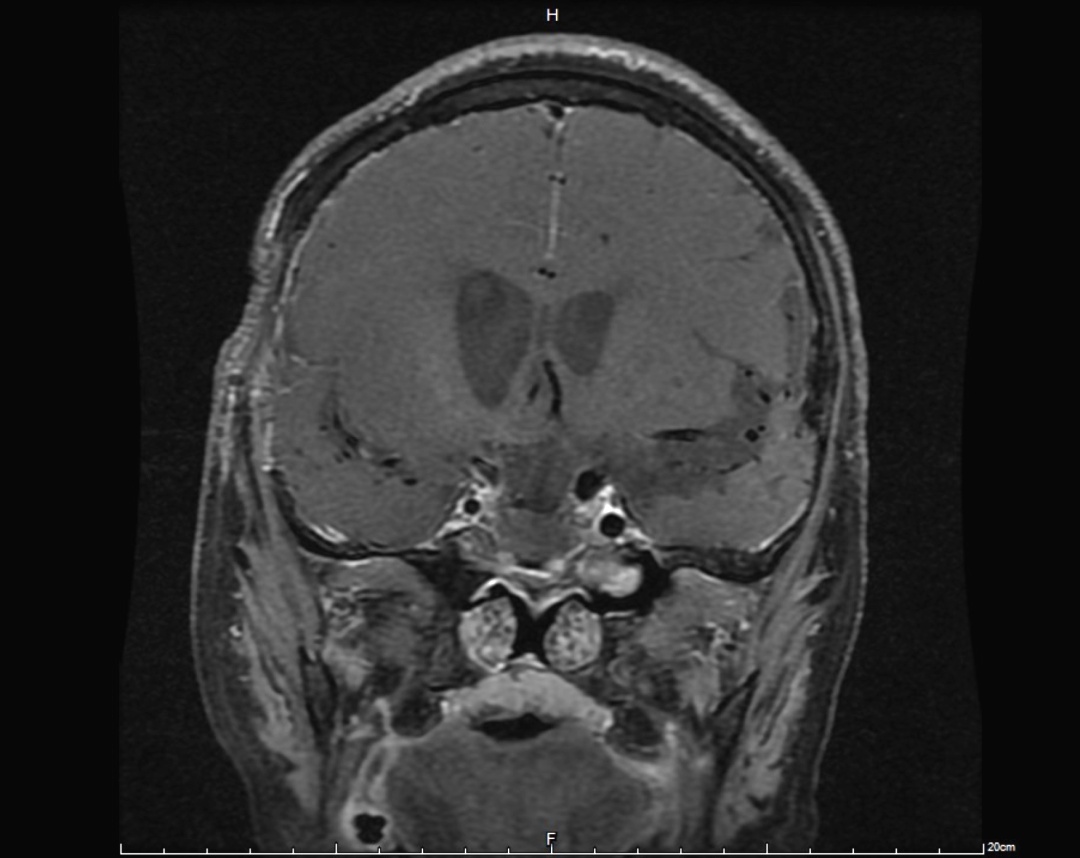

手术后